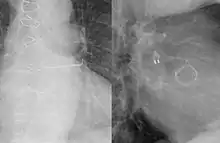

![]() A left atrial appendage occlusion method similar to the WATCHMAN device. | |